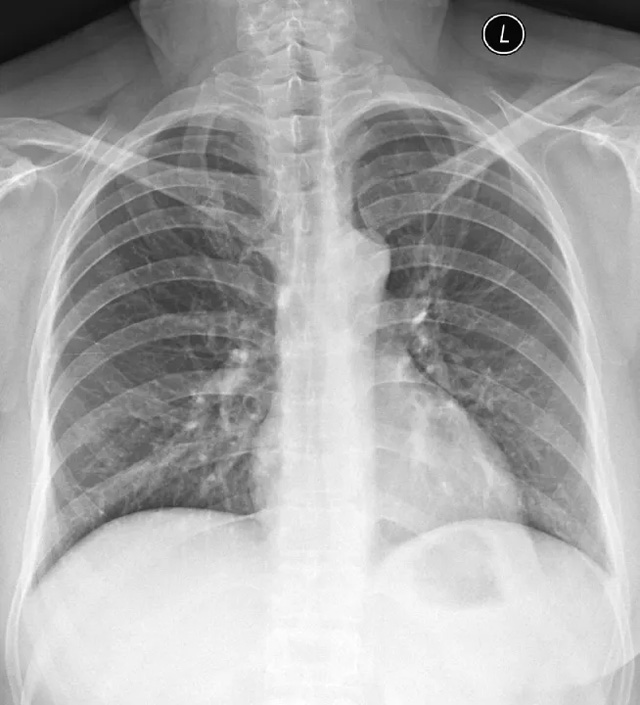

X線定位真空輔助旋切術(shù)是對(duì)臨床觸診和B超檢查均為陰性而X線片顯示的微小病變在X線立體定位引導(dǎo)下,將真空旋切刀置入乳腺可疑病灶區(qū)進(jìn)行旋切及組織病理學(xué)檢查的一種乳腺微創(chuàng)新技術(shù)。